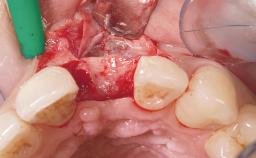

A 30-year-old female patient was referred to the office for the treatment of tooth 11. Her chief concern at the initial visit was to inquire, “Why is my tooth pink?” Upon clinical examination, it was determined that tooth 11 had a previous history of trauma and that the clinical crown had become noticeably pink in color as a result of internal resorption. This diagnosis was confirmed radiographically, indicating a large radiolucency involving the central and distal portions of the clinical crown. It was determined that restoration of this tooth was not possible, and that extraction was indicated. The presence of a mid-line diastema, which the patient wanted to reproduce, directed the treatment plan for tooth replacement utilizing a dental implant.

Bone Augmentation Horizontal|Simultaneous

Augmentation Materials Autogenous chips|Membrane

Placement Protocol Immediate implant placement